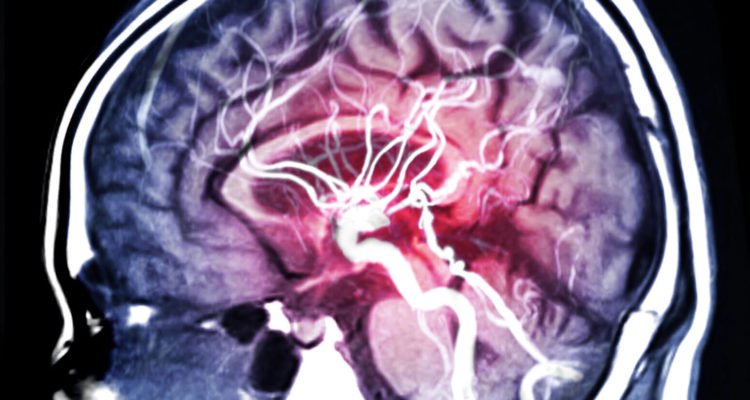

Geriamieji kontraceptikai gali padidinti insulto riziką kai kurioms moterims, ypač rūkančioms. Dėl to vyresnėms nei 35 metų pacientėms, kurios rūko, nerekomenduojama vartoti šių vaistų. Ankstesni tyrimai parodė, kad II-IV kraujo grupės taip pat gali padidinti insulto riziką.

Tyrėjai nustatė, kad rūkančioms ir geriamuosius kontraceptikus vartojančioms moterims rizika patirti insultą buvo beveik penkis kartus didesnė nei moterims, kurios nevartojo šių vaistų ir neturėjo įpročio rūkyti. Kraujo grupė, išskyrus I, didino ankstyvojo insulto riziką rūkančioms ir geriamuosius kontraceptikus vartojančioms moterims. Rizika padidėjo beveik du kartus.